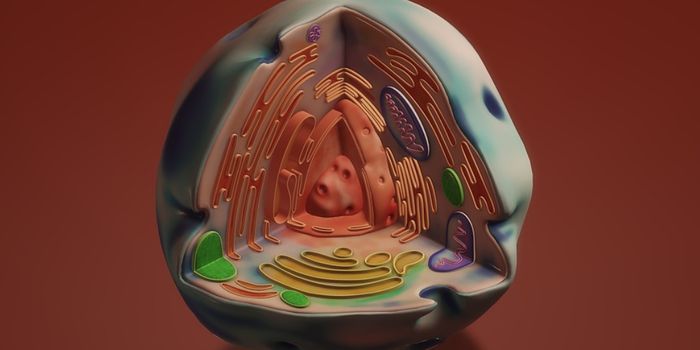

AUG 26, 2024Genetics & GenomicsCells are defined by the genes they express. In human cells, there are thousands of different protein coding genes, and ...